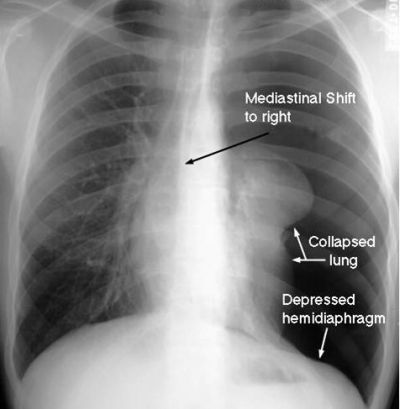

בהאזנה מעל הריאות ניתן לשמוע כניסת אוויר מופחתת, נשימה ברונכיאלית בצד הנפגע, ובניקוש - טימפניזם. בצילום חזה ניתן לראות תמט ריאה עם גבול ריאה המרוחק מדופן בית החזה (תצלום 12.16) המיצר ללא סטיה וגובה הסרעפות שווה, כמו כן ניתן למצוא אמפיזמה תת-עורית (תצלום 13.16). ממצאים אלה נראים ברור יותר ב-CT חזה.

בצילום חזה של נפגע עם חזה אוויר בלחץ נראה בנוסף לסמני חזה אוויר גם דחיקה של המייצר לכיוון הנגדי וגם דחיקה של הסרעפת כלפי מטה (תצלום 14.16).